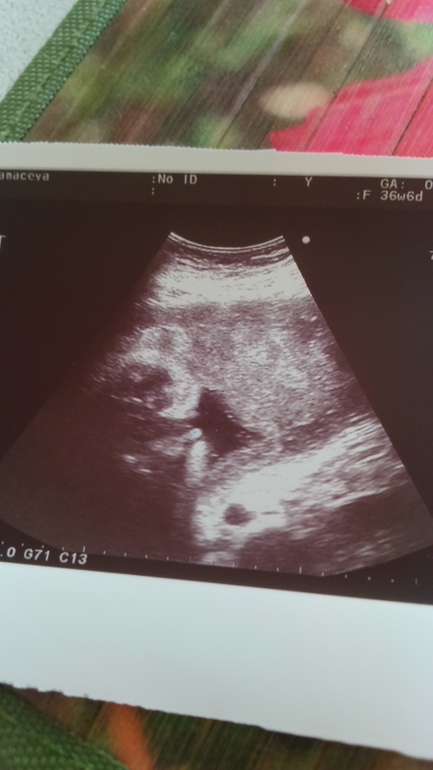

Наши будни, наши неделькиДевочки, гляньте, как вам кажется на что похоже?? Вообще это половые губки, но две моих подружки сказали, похоже на яички и писюн.... Я в замешательстве... не ужели правда похоже?